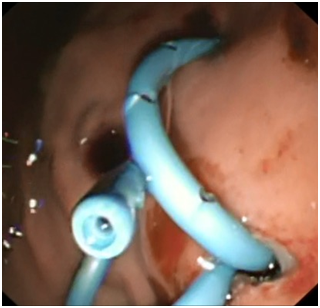

Figure 3A & 3B A guidewire is passed after cyst puncture and balloon dilatation of the tract.

Upon presentation to our hospital, he was complaining of intermittent abdominal pain, post prandial abdominal fullness, however he was not ill and abdominal examination showed distended abdomen with fullness of the left upper quadrant and scars of previous drain insertion. His investigations showed WBC 11.86, Hb 12.8 g/dl, Amylase 123, and Lipase 818. CT Abdomen showed a significant increase in the size of the pancreatic pseudocyst (8x8x12cm). Consent was obtained from his parents for EUS guided cystogastrostomy. Prophylactic antibiotic using Ciprofluxacin was given before and after the procedure for three days. The Olympus EVIS LUCERA Ultrasound Gastrovideoscope GF-UCT 260, 14.6 mm distal tip was introduced easily through the esophagus to the stomach. This showed a large homogenous cyst measuring 8X9 cm, with a clear wall that was adherent to the gastric wall with no intervening blood vessels. This was punctured with 19 G needle and 30 ml of clear aspirate was sent for chemistry and cytology. A guide wire with two loops was formed in the cyst over which a needle knife was used to puncture the gastric wall and create an opening which was dilated to 4 mm. Two pig tail stents 7 Fr 4 cm were placed to drain the cyst. Post drainage, he was doing well, with no signs of complications, and resolution of abdominal pain and distension. He continued to receive antibiotics and was discharge after 2 days of the procedure in a satisfactory condition. His amylase and lipase levels went down to 109 & 631 respectively. The amylase level in the fluid was 7425 u/l, normal CEA level and cytology showed cystic fluid with no malignant cells. Six weeks later, MRI showed complete resolution of the collection and a repeat EUS confirmed resolution of pancreatic pseudocyst. The stent was removed and currently the patient is well and asymptomatic (Figure 4).